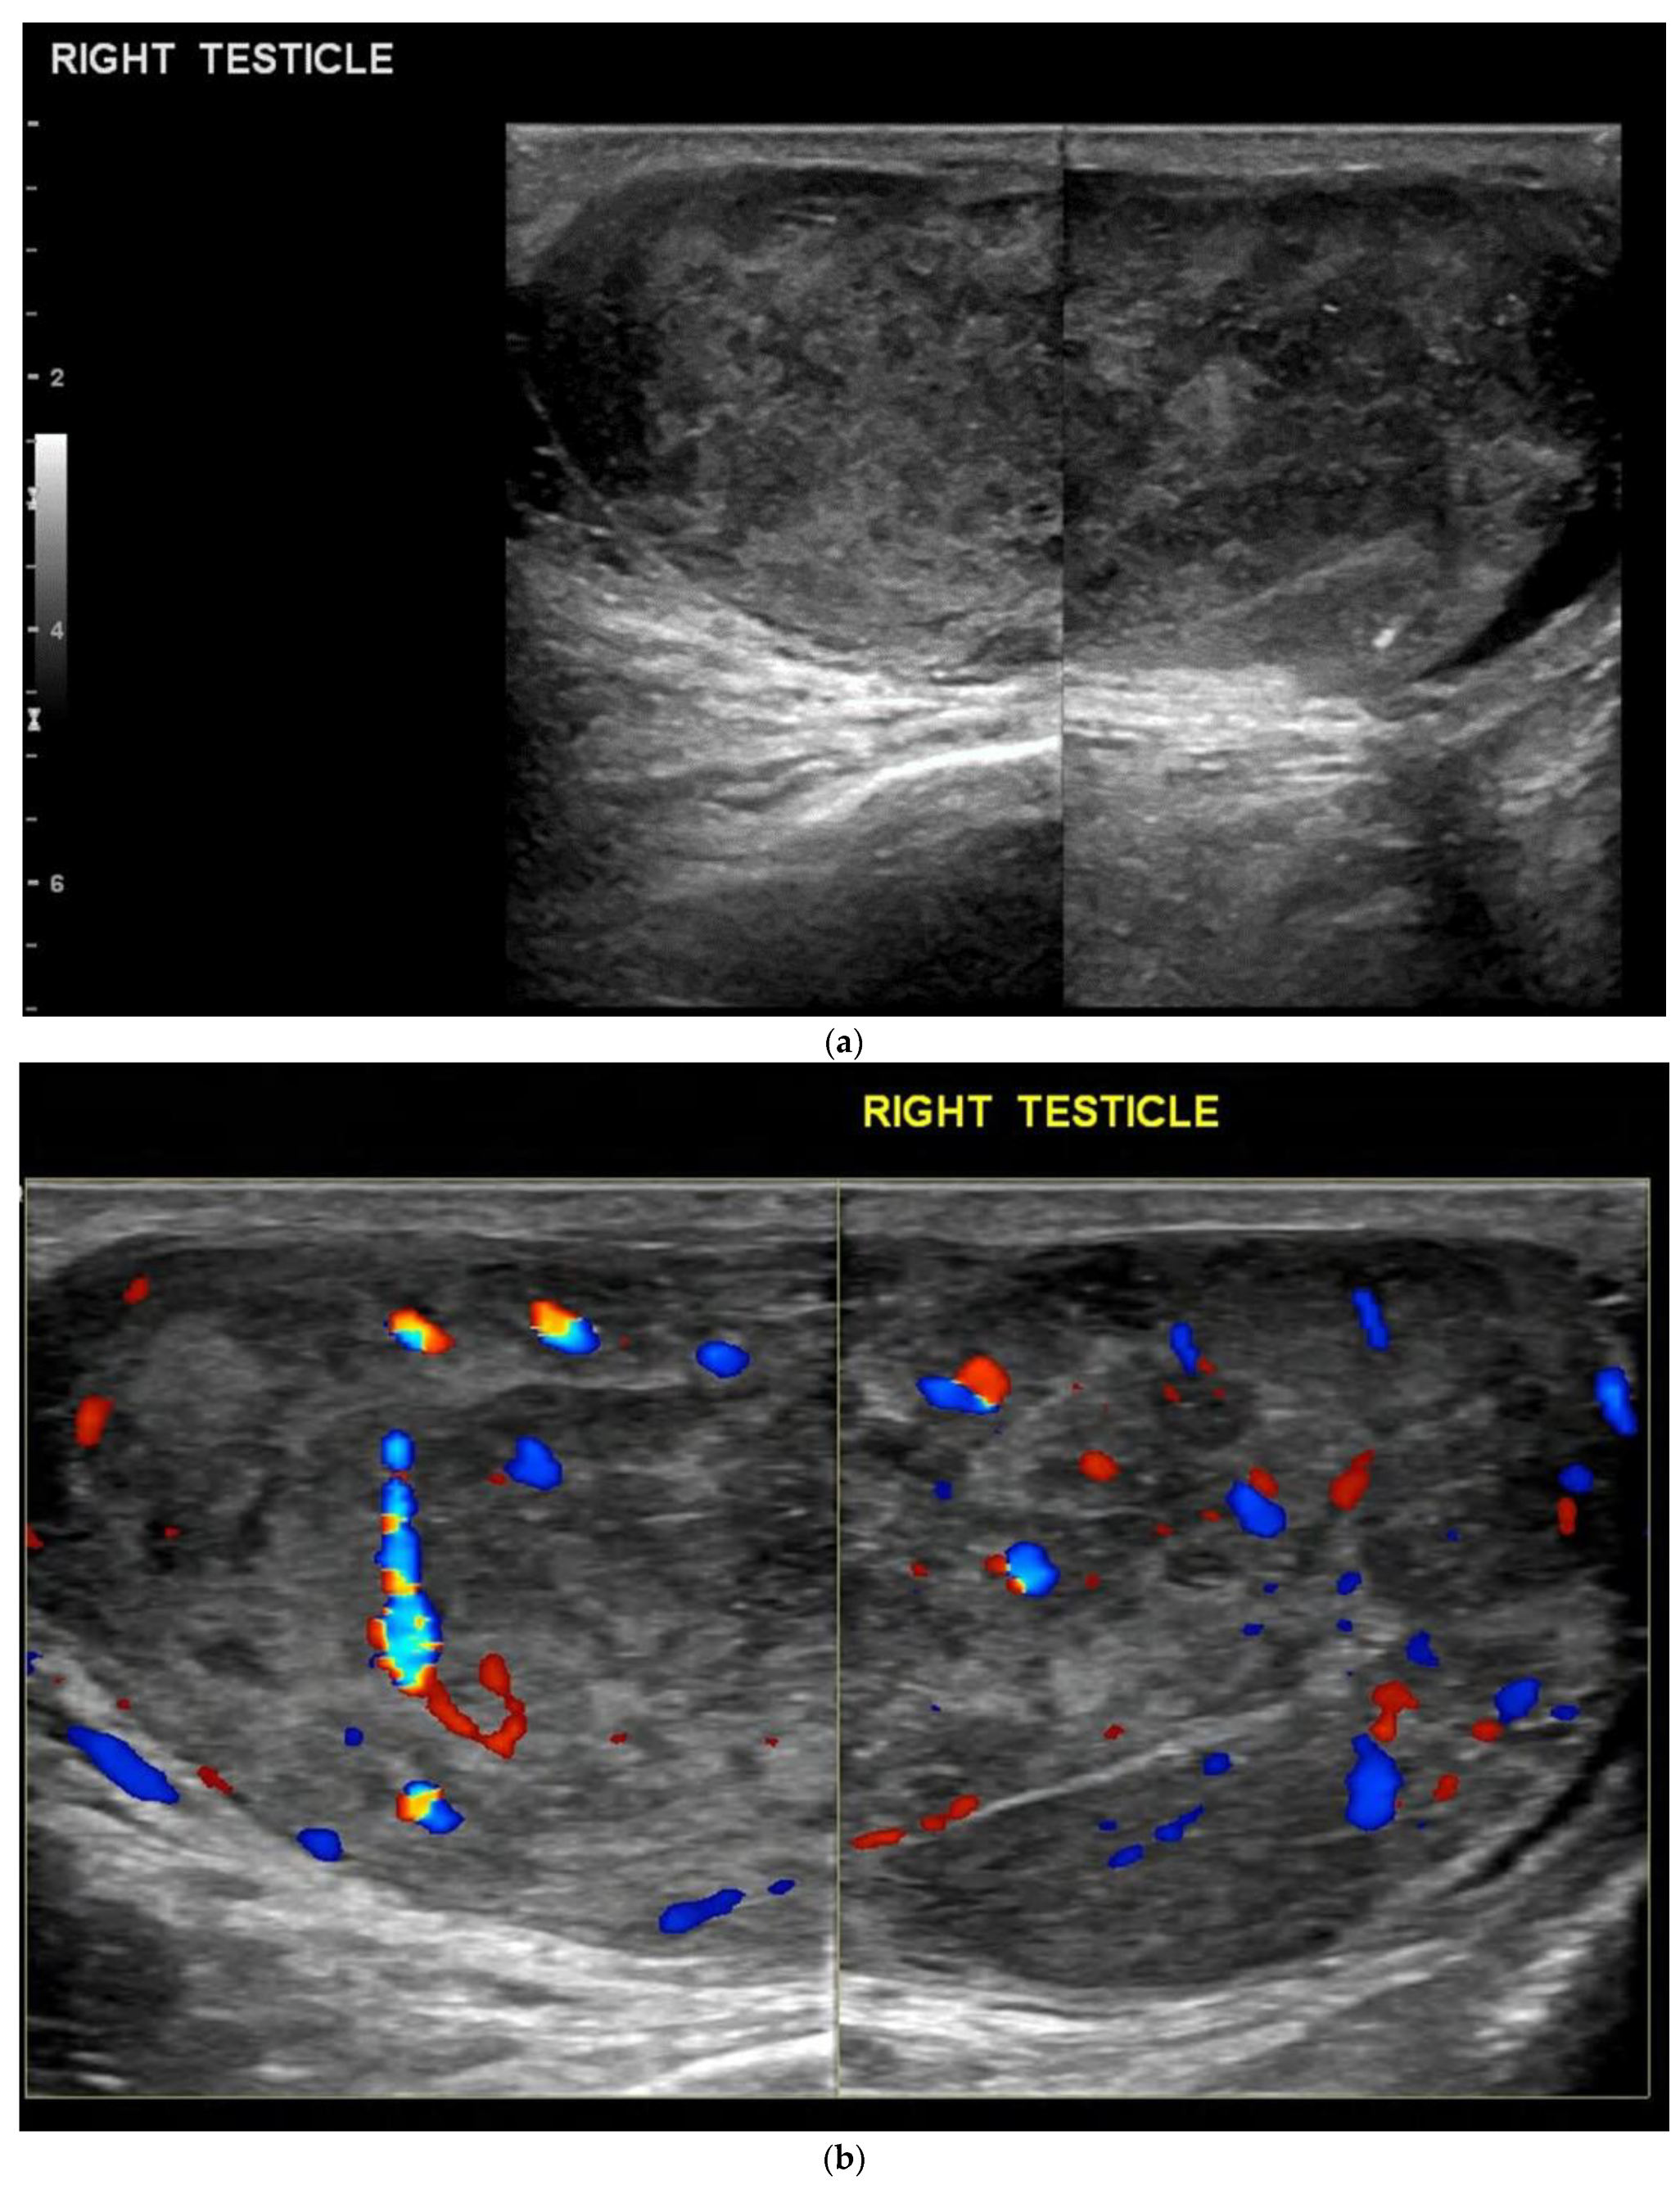

4.1. Seminomatous Germ Cell Tumour

| Seminomas | Homogenous and hypoechoic Well circumscribed Occasionally contain cystic components or calcifications |